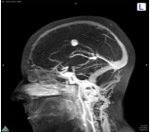

B: NEURONAVIGATION

MRi Tractography

Pre

Post